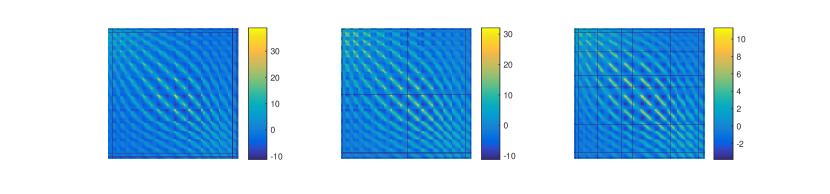

From a practical perspective, it is crucial to understand how the different parts of the brain interact, which is sometimes known as functional connectivity. A possible way to understand these interactions is by analyzing the covariance function associated with the signals describing the cerebral activity of an individual on the brain space (Fransson et al., 2011; Lee et al., 2013; Li et al., 2009). More recently, the interest has shifted from this static approach to a dynamic approach. In particular, for a single individual, it is of interest to understand how these covariance functions vary in time. This is a particularly active field, known as dynamic functional connectivity (Hutchison et al., 2013). Another element of interest is understanding how these covariance functions vary among individuals. In Figure 2, we show the covariance matrices, on the sensors space, computed from the MEG signals of three different subjects.

Consider now sample covariance matrices , each of size , representing different connectivity maps on the sensors space. Three of such covariance matrices, associated with three different individuals, are shown in Figure 2. Recall moreover that we denote with the brain surface template and with the set of subject-specific forward operators, relating the signal at the pre-specified points on the cortical surface with the signal detected on the sensors.